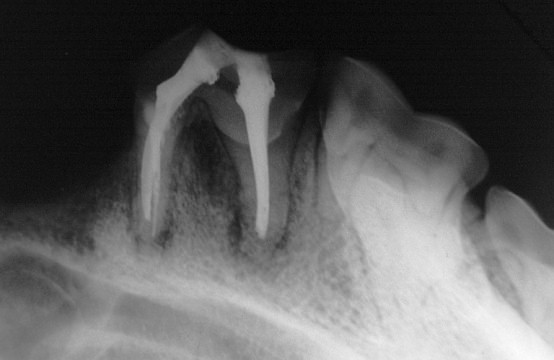

Röntgen Kontrolle der Füllung